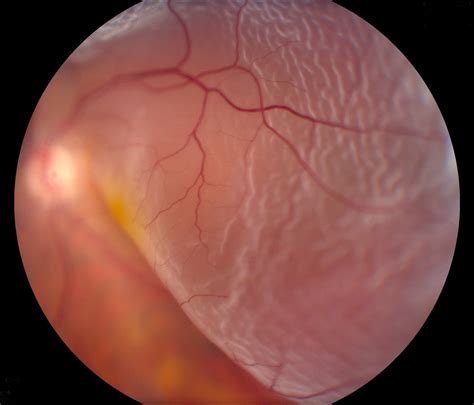

Retinal Detachment | Retina | MedlinePlus